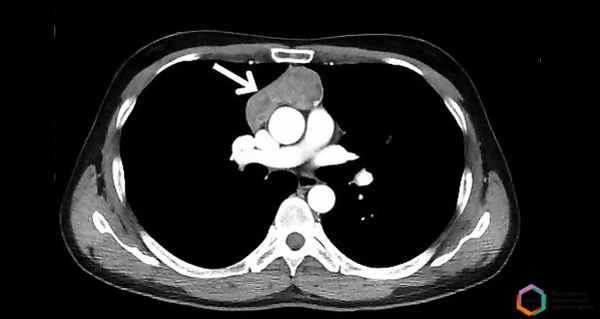

Мультиспиральная компьютерная томография (МСКТ) с контрастированием.

В марте 2019 года у пациента появились трудности с дыханием и глотанием, поэтому он был госпитализирован с подозрением на ангионевротический отек. После осмотра ЛОР-врачом ангионевротический отек исключен, а неврологом установлен диагноз: миастения прогрессирующая форма, бульбарный тип. При дообследовании в МКНЦ проведены УЗИ и КТ и выявлено опухолевое образование тимуса.

Полная диагностика тимомы включает также современные диагностические исследования – КТ, МРТ, — которые позволяют получить точные данные о расположении опухоли, ее размерах, распространенности патологического процесса и другую информацию, необходимую для подбора качественного лечения.